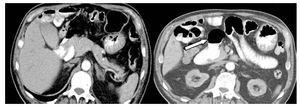

¿ Figura 3. Imagen tomográfica de un Dd de 5.9 cm por 3.9 cm de diámetro.

En siete casos (14%) el Dd causaba un efecto de masa sobre estructuras adyacentes (rango de diámetro de 2.1 a 7.1 cm). Además, el Dd fue condicionante de pseudolesión focal en la cabeza pancreática en 14 casos (28%). Se identificaron tres casos (6%) de Dd yuxtapapilar, uno de ellos que se complicó con sangrado del tubo digestivo y fue el de mayores de dimensiones (7.1 cm por 4.4 cm). No se identificaron Dd asociados a coledocolitiasis (Figura 4).

¿ Figura 4. Imágenes axiales, fase con contraste oral, en una mujer de 75 años con hallazgo incidental de gran Dd único, complicado con sangrado digestivo alto, yuxtapapilar, de 7 cm, ubicado en la segunda porción de duodeno (zona periampular).